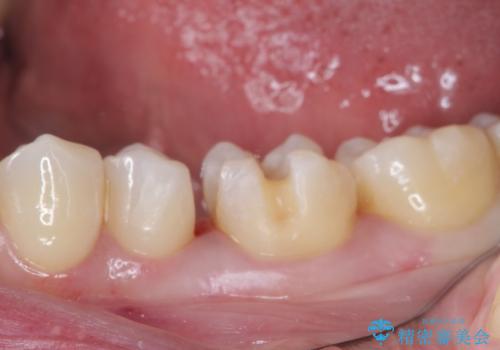

- 銀歯をセラミックにしたいとのことで来院された患者様です。

まず麻酔をして銀歯を外し、むし歯を除去し、形を整えて型取りします。

そして次の来院時、セラミックインレーを装着し、噛み合わせなどの調整を行います。

それを左右に分けて行いました。